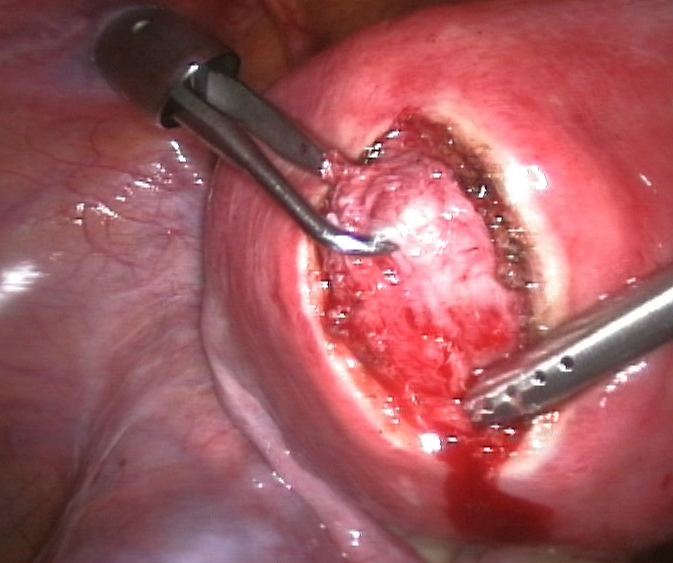

증상이 있는 경우에는 치료가 필요하다.[79] 임신을 희망하는 경우 GnRH유사체 투여로 근종을 축소시킨 후 근종 절제술을 시행하고, 임신을 희망하지 않거나 악성 소견이 보이는 경우에는 단순 자궁 절제술을 시행한다.[82] 근종 절제술에는 복식(개복), 질식, 복강경, 자궁경 하 방식이 있다. 자궁경 하 방식은 장경 3cm 정도의 점막하 근종에 적합하다. 수술 외의 치료법으로는 자궁 동맥 색전술[82]이나 고강도 집속 초음파 치료 등이 알려져 있다.

근종 절제술은 하나 이상의 자궁근종을 제거하는 수술이다. 보존적 치료 옵션이 실패하고, 가임력을 보존하거나 자궁을 유지하려는 환자에게 보통 권장된다.[60]

근종 절제술에는 세 가지 유형이 있다.

- ''자궁경 수술'' 근종 절제술(''경자궁경부 절제술''): 절제경, 질과 자궁경부를 통해 삽입하여 조직을 절단하는 데 고주파 전기에너지를 사용할 수 있는 내시경 도구를 사용하거나 이와 유사한 장치를 사용하여 자궁근종을 제거.

- ''복강경'' 근종 절제술: 배꼽 근처의 작은 절개를 통해 수행. 의사는 복강경과 수술 도구를 사용하여 자궁근종을 제거. 복강경 근종 절제술이 개복 근종 절제술보다 낮은 이환율과 더 빠른 회복을 보인다.[61]

- ''개복'' 근종 절제술(''개복'' 또는 ''복부'' 근종 절제술): 자궁근종을 제거하는 가장 침습적인 수술 절차. 의사는 복벽에 절개를 가하고 자궁에서 자궁근종을 제거.

복강경 근종 절제술은 개복 수술보다 통증이 적고 입원 기간이 짧다.[62] 15,000명의 환자를 분석한 결과, 근종 절제술을 받은 환자는 그 후 5년 동안 자궁근종 관리를 위한 추가 시술(자궁 절제술 포함)이 UAE를 받은 환자보다 적게 필요했다.[63][64]

증상이 있는 경우에는 치료가 필요하다.[79] 치료법으로는, 임신을 희망하는 경우 GnRH유사체 투여로 근종을 축소시킨 후 근종 절제술을 시행하고, 임신을 희망하지 않거나 악성 소견이 보이는 경우에는 단순 자궁 절제술을 시행한다.[82] 근종 절제술에는 복식(개복), 질식, 복강경, 자궁경 하 방식이 있다. 자궁경 하 방식은 장경 3cm 정도의 점막하 근종에 적합하다. 수술 외의 치료법으로는 자궁 동맥 색전술[82]이나 고강도 집속 초음파 치료 등이 알려져 있다.